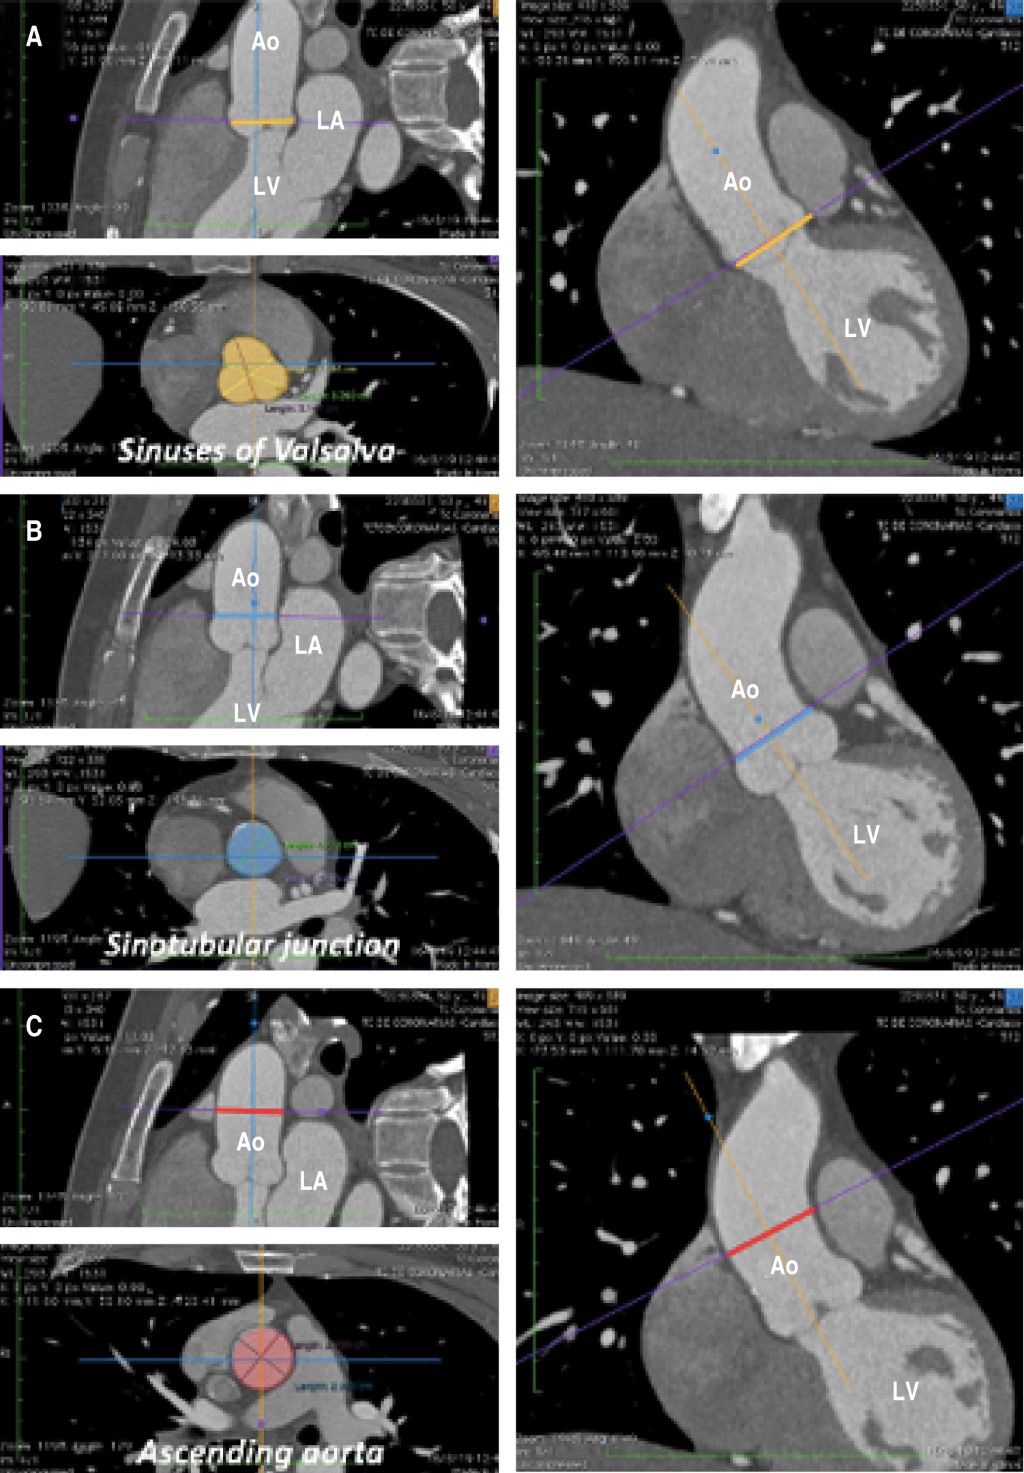

Introducción: Los rasgos específicos de la raíz aórtica parecen tener algunas implicaciones clínicas y pronósticas, y las diferencias relacionadas con el sexo se han descrito previamente. Sin embargo, faltan datos sobre la población mexicana. Objetivos: Describir las discrepancias relacionadas con el sexo con respecto a las características de la raíz aórtica en un análisis estructural y funcional. Material y métodos: Se analizaron los datos de hallazgos de la tomografía computarizada cardiaca de la raíz aórtica en 71 pacientes mexicanos con válvula aórtica de trivalva, sin estenosis valvular ni antecedentes de aneurisma de la aorta. Se dividió la población para describir las desviaciones específicas por sexo; mujeres 53.5% (n = 38) y hombres 46.5% (n = 33). La mediana de edad fue de 56 años (IQR: 49-64) con una prevalencia similar de hipertensión, diabetes, tabaquismo y dislipidemia. El peso, altura y área de superficie corporal (ASC) fueron significativamente más bajos en las féminas, sin divergencias en el índice de masa corporal. No hubo disparidades notorias con respecto a la excentricidad del anillo aórtico durante la sístole y la diástole y la angulación de la aorta durante la diástole. No obstante, la angulación aórtica durante la sístole fue mayor en mujeres y las dimensiones del anillo aórtico en sístole resultaron ostensiblemente más altas en varones. Las magnitudes de la raíz aórtica se revelaron superiores en los hombres, pero cuando se indexaron a ASC fueron más elevadas en las señoras. Se encontró un anillo aórtico pequeño en 71% de las féminas y 18.1% de los varones, y una raíz aórtica pequeña fue significativamente mayor en los señores en comparación con las señoras (30.3% versus 2.6%, p = 0.001). Conclusiones: Características individuales como el peso, estatura y ASC tienen consecuencias al comparar las dimensiones aórticas. Las diferencias de estos parámetros entre sexos, como la baja estatura corporal en las mujeres mexicanas, podrían explicar la alta prevalencia de un anillo aórtico pequeño, especialmente cuando la medida se indexa por altura del cuerpo y las otras particularidades de la aorta a diferentes niveles. Las implicaciones clínicas de estos hallazgos permanecen inciertas.

Figura 1